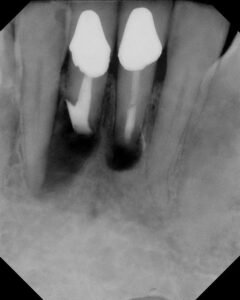

Because of the resorption at the apex of #25, a traditional root end preparation and filling was not possible with removing too much tooth structure. In this case, we bonded Geristore on the root apex and tried to “cap” the apex. Retrofill #24 is MTA.